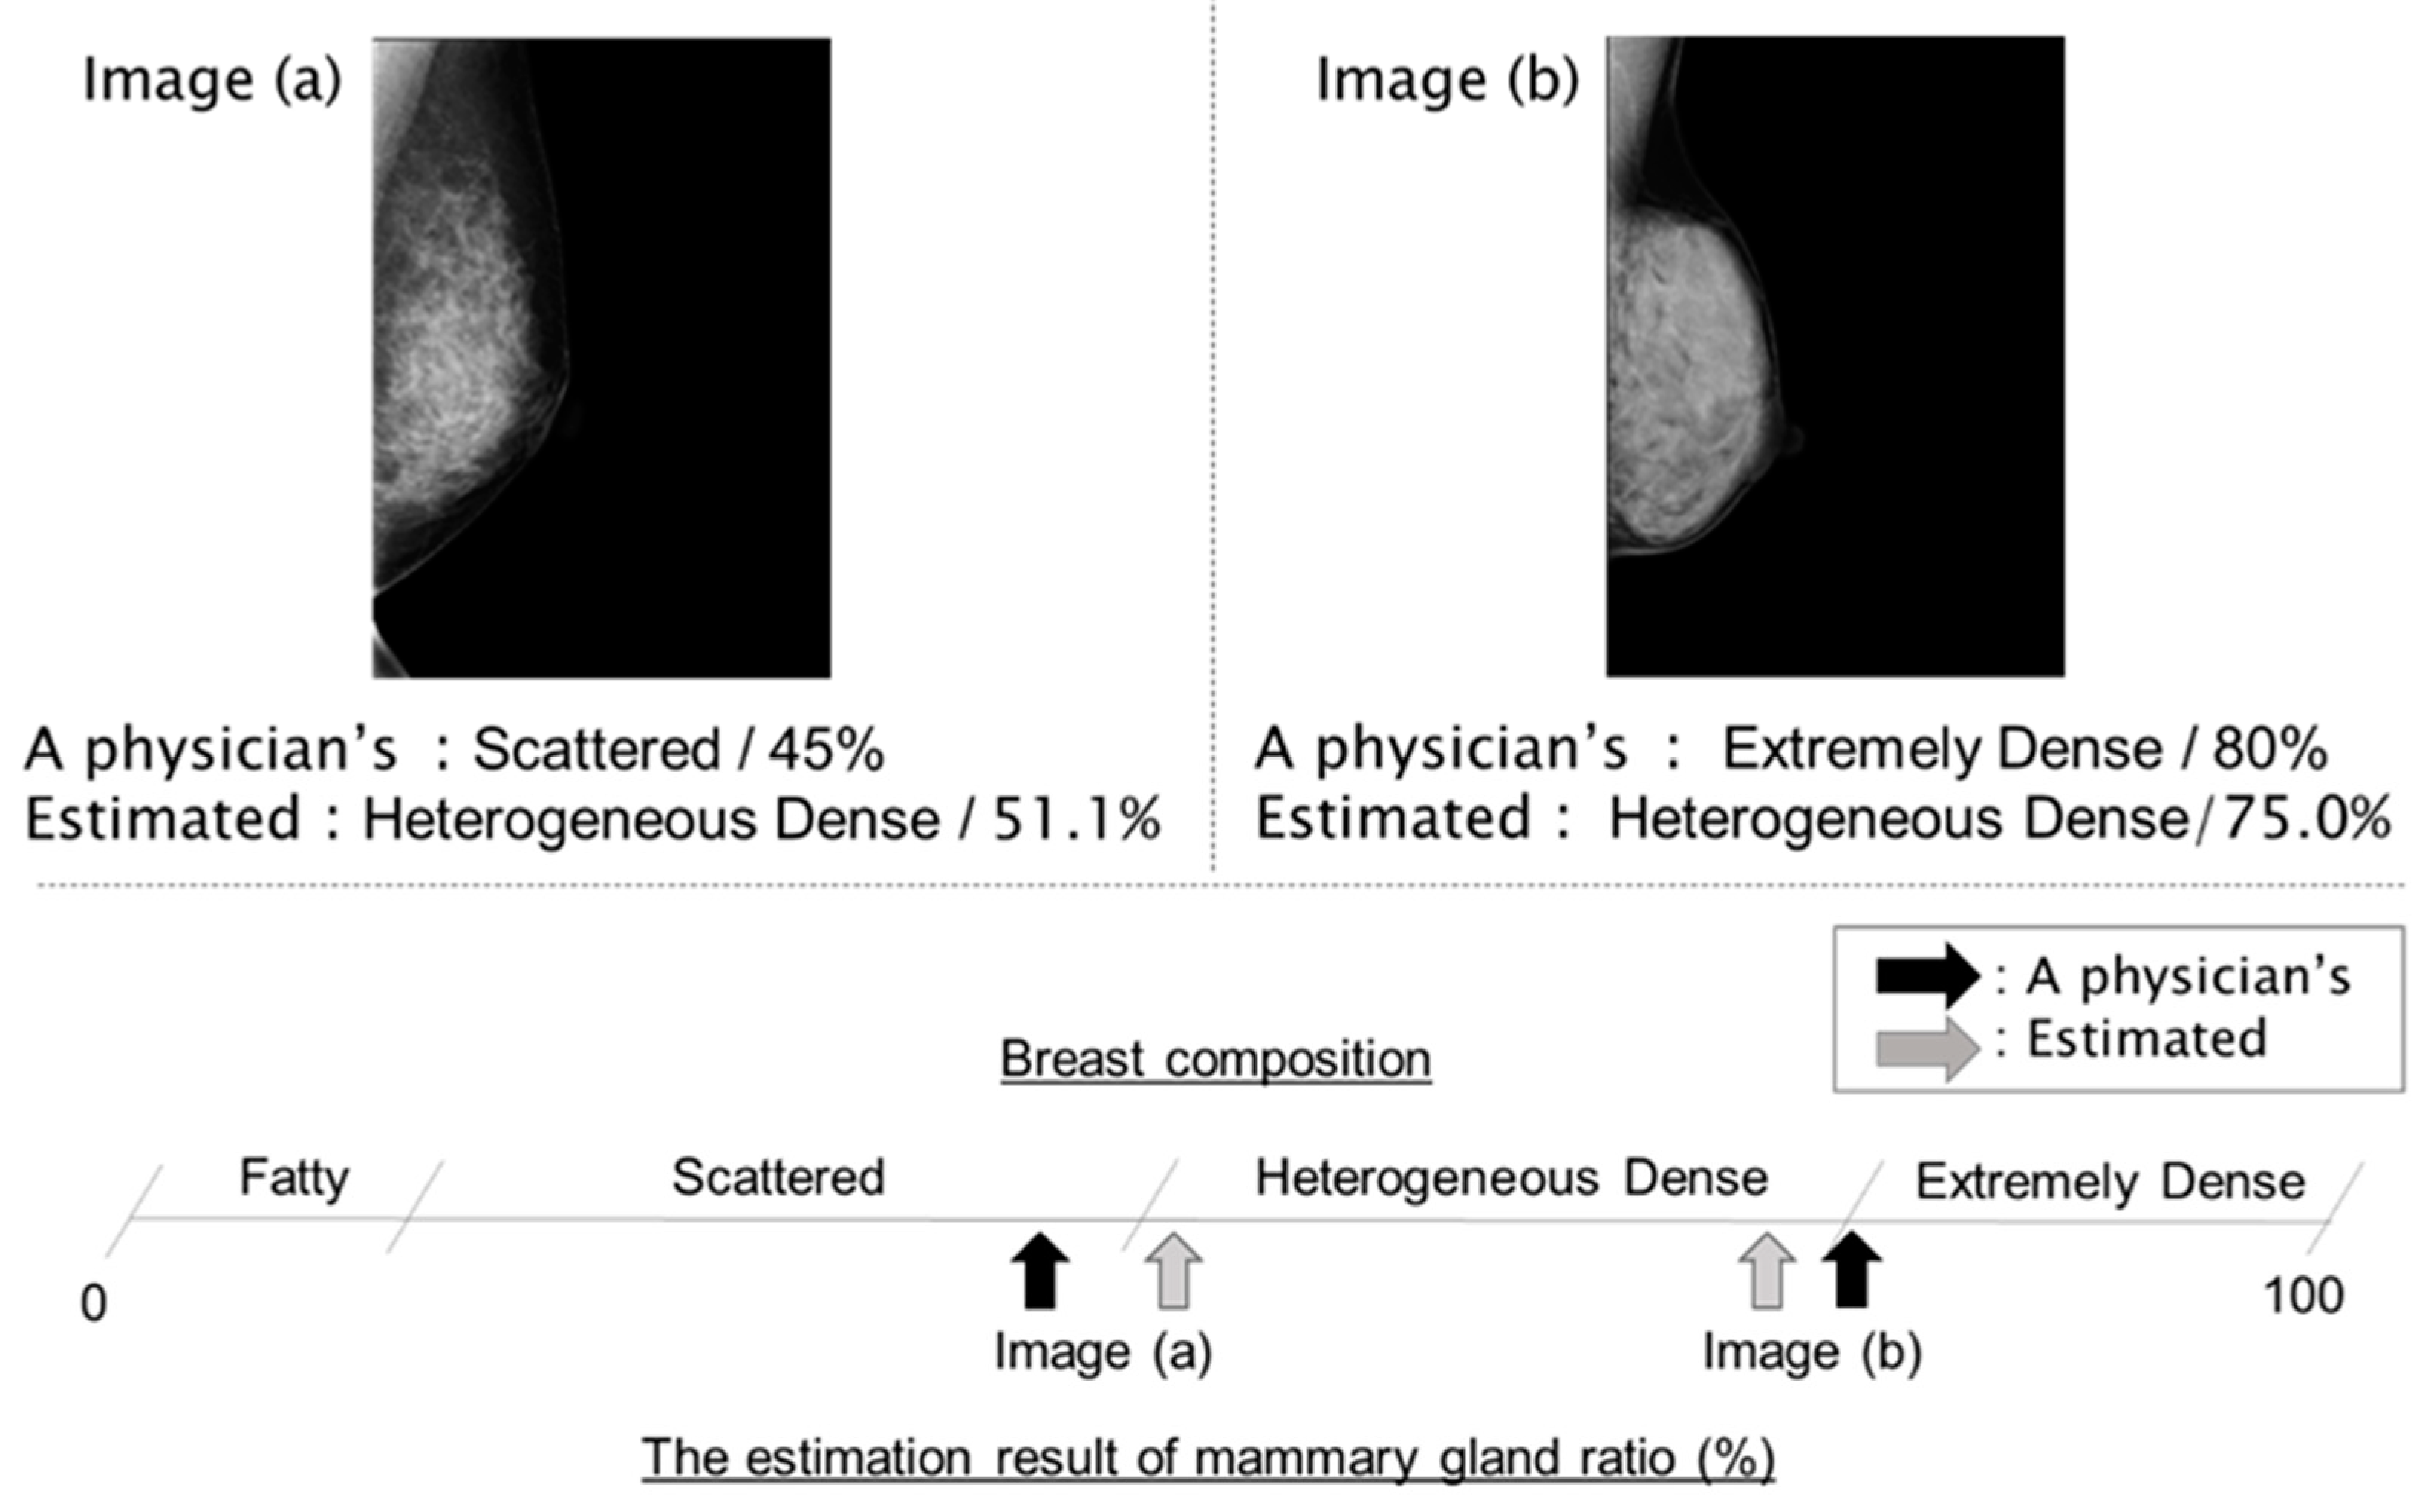

3. Results

4. Discussion